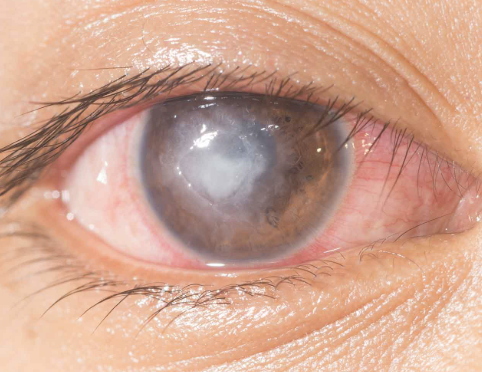

Cataracts

Abnormal Finding for 10. Inspect the cornea and lens

Opacities of the lens

Corneal Ulcer

One of the 6 Corneal Abnormalities

An open sore on the cornea, often resulting from untreated keratitis or corneal abrasions

Can lead to permanent scarring and vision loss if not promptly treated

Nuclear Cataract

One of the 4 Lens Abnormalities

Appear gray when seen with a flashlight

Appear as a black spot against the red reflex when seen through an opthalmoscope

Peripheral Cataract

One of the 4 Lens Abnormalities

Looks like gray spokes that point inward when seen with a flashlight

Look like black spokes that point inward against the red reflex when seen through an opthalmoscope